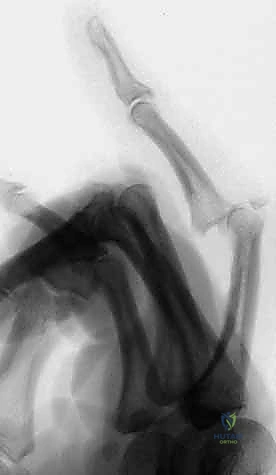

- Identify Distal Wire Level: Under image intensifier guidance, identify an appropriate level in the distal half to two-thirds of the middle phalanx. This placement must be distal to any fracture extension in the shaft of the middle phalanx to ensure adequate purchase in healthy bone. Mark this level on the skin.

> PEARL: For pilon fractures with significant distal extension, the distal wire can be placed as far distally as the head of the middle phalanx, or even near the center of rotation of the distal interphalangeal (DIP) joint. The middle phalanx is often narrowest proximally, so a more distal placement often provides a wider bone segment for easier and more secure wire placement. I have never encountered a fracture so distal that adequate fixation could not be achieved.

Figures 1D and 1E (TECH FIG 1D,E) illustrate finding and marking the position of the distal wire. Note how this placement is more distal than average, towards the head of the middle phalanx, due to an associated DIP joint injury, providing ample bone for fixation.

-

Initial Distal Wire Insertion: Similar to the proximal wire, insert the 1.1-mm K-wire percutaneously, aiming for the center of the middle phalanx. This wire must be perpendicular to the long axis of the finger and, crucially, parallel to both the plane of rotation of the PIP joint and the previously inserted proximal wire. This parallelism is essential for creating a functional dynamic construct.

Fluoroscopic Confirmation (Partial Insertion): Insert the wire partially through the middle phalanx and check its position carefully with both PA and lateral views on the image intensifier.

*Figures 1F and 1G (TECH FIG 1F,G) confirm the insertion and position of the distal wire on the image intens